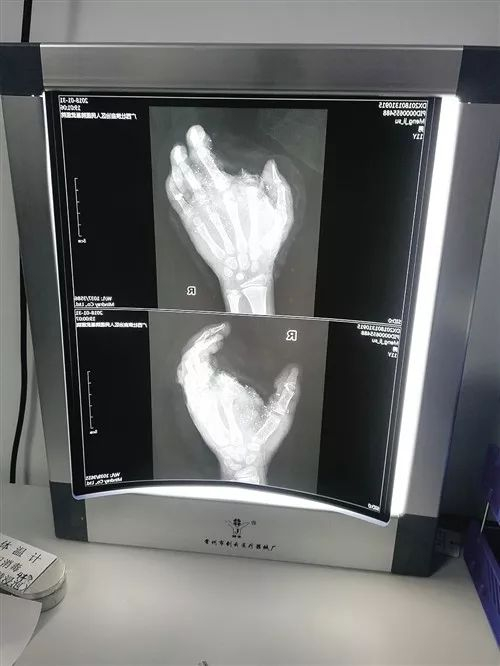

CT显示小蒙右手受伤情况

兰天兵说,小蒙的右手伤得很重,右食指炸飞了,只剩下一点点,拇指、中指和尾指没有了血供,整个手掌和手背的血管炸没了,而且右眼暂时看不见。“要恢复血供必须要有血管,第一时间必须做手部手术。”